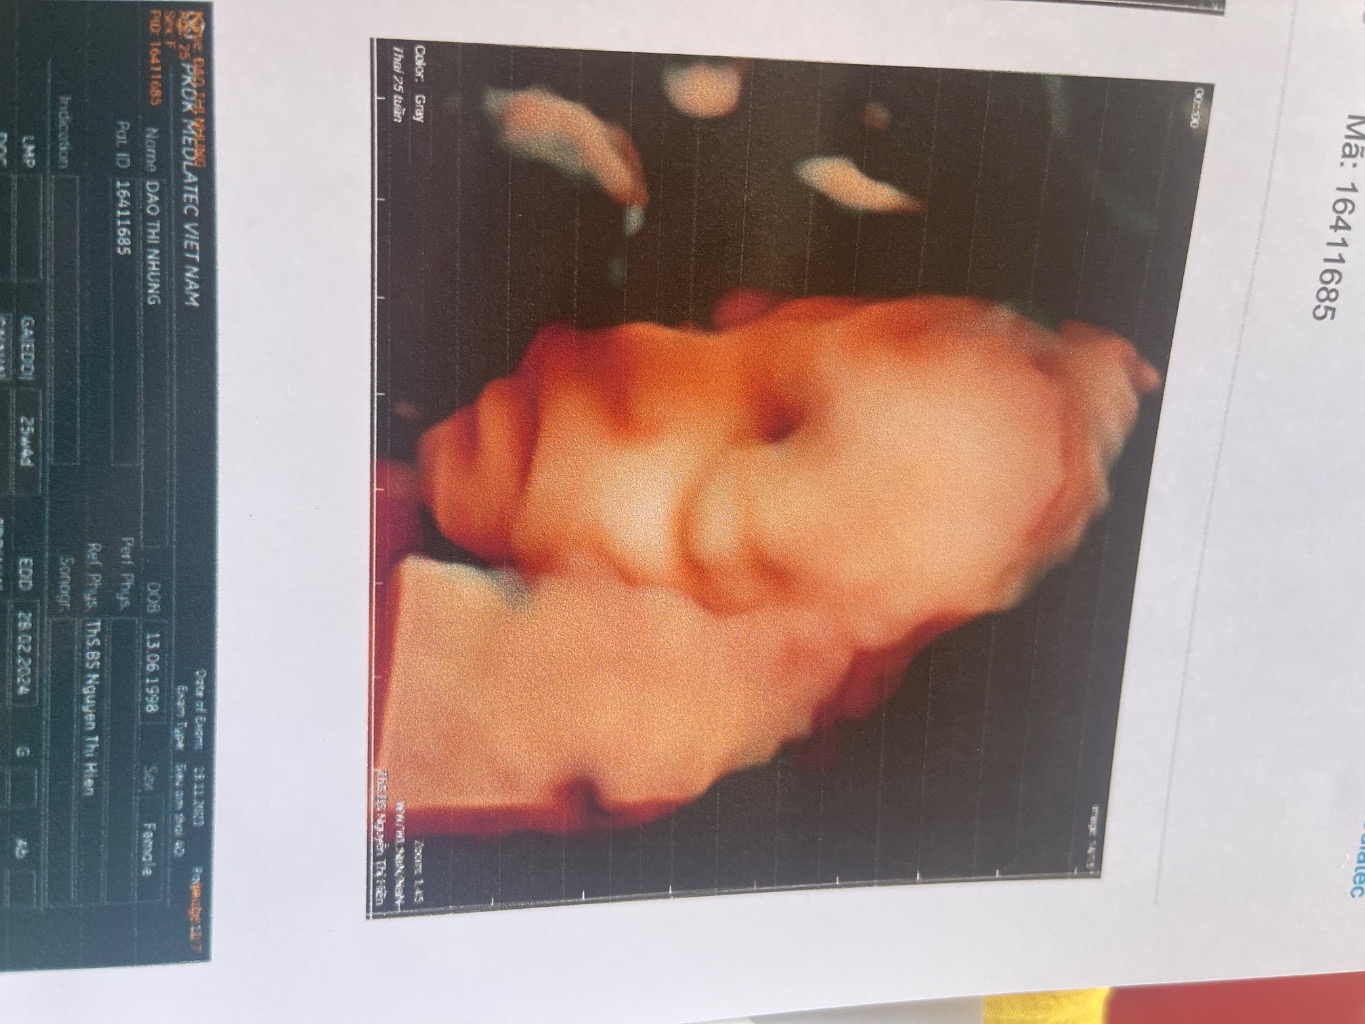

Đào Thị Nhung